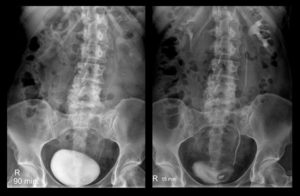

Цистографія — це метод дослідження в урологічній практиці, що дозволяє візуалізувати сечовий міхур. Урографія — діагностичне захід, спрямований на обстеження нирок. Обидва методу проводяться із застосуванням рентгенконтрастної речовини. Оцінка стану сечового міхура і нирок у дітей робиться на основі відмінностей між знімками, зробленими до і після введення контрасту. Необхідність використання рентгенконтрастної речовини обумовлена тим, що воно забарвлює уражені місця нирок і сечового міхура в яскраві кольори, які помітно виділяються на знімку.

- Перший знімок. Його роблять до моменту потрапляння контрасту в організм пацієнта.

- Введення катетера та його заповнення контрастною рідиною. Її кількість визначається віком. Для пацієнтів молодше 12 років норма становить 50-100 мл, після зазначеного віку — 200-300 мл.

- Знімки в різних проекціях з контрастним речовиною. Чим більше положень буде приймати пацієнт, тим вище ймовірність розглянути приховану патологію.

- Зняття катетера. Після того, як він це зробить, він повинен ще раз зафіксувати порожній сечовий міхур.

- Аналіз отриманих даних. По закінченню процедури фахівець готує висновок.

Багато мам після здійснення обстеження відразу ж спрямовуються до лікаря для отримання розшифровки результатів. Завдяки контрастній речовині, який сприяє виділенню уражених місць на фото, лікар може розглянути наступні патології: